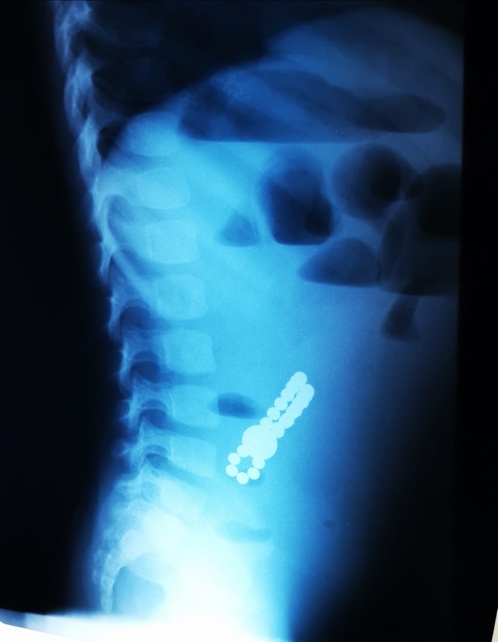

Dr. Adriana Constantineanu, medic specialist în chirurgie pediatrică atrage atenția asupra pericolului din spatele jucăriilor cu magnet. Acestea îi pot distra pe copii și pot fi fascinați de multitudinea de culori vii care îi duce cu gândul pe cei mici la bomboane, înghițindu-le.

Acești magneți sunt foarte puternici, iar ingestia lor poate duce la probleme gastrointestinale grave. Odată înghițiți sunt atrași unul spre altul chiar dacă se găsesc în secțiuni diferite ale tubului digestiv. O ansă intestinală prinsă între acești magneți se poate perfora ducând la tratament chirurgical de urgență. În secția noastră, de la începutul anului s-au prezentat trei cazuri, două fete și un băiat, cu vârste cuprinse între 2 și 4 ani. Aceștia au suferit perforații la nivelul intestinului subțire și au necesitat intervenții pentru îndepartarea porțiunii de intestin afectate”, a precizat dr. Adriana Constantineanu.